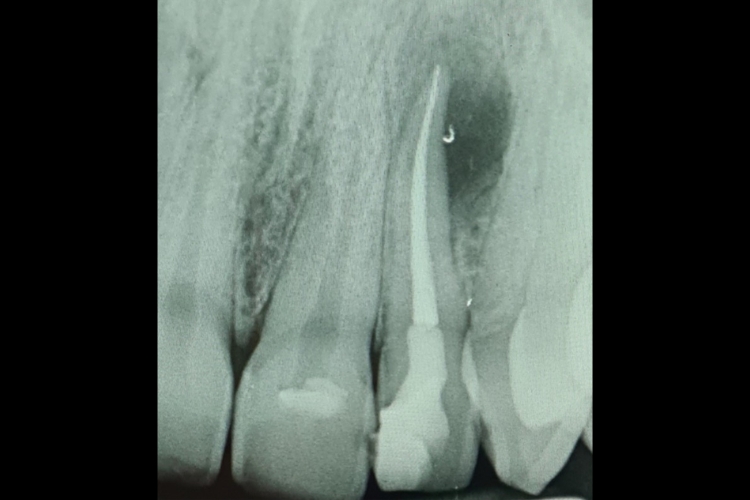

Root Canal Treatment

The example above is of a high-quality root canal undertaken by Dr Raj Koner. Root Canal Treatment is an important dental procedure to help relieve toothache and save…